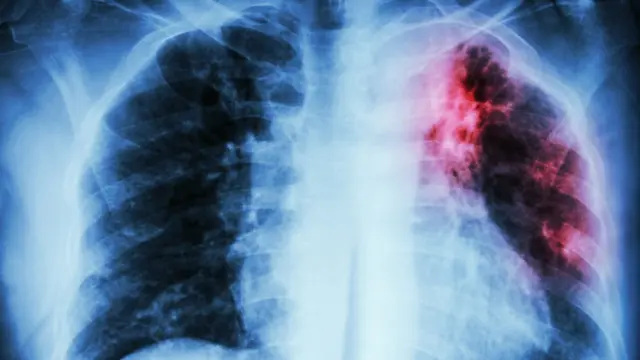

3. Tuberculosis

Fuente de la imagen, Getty Images

La tuberculosis es una enfermedad causada por la Mycobacterium tuberculosis, una bacteria que casi siempre afecta a los pulmones. Es curable y prevenible, señala la Organización Mundial de la Salud.

Y en el continente americano, como en el mundo, la tuberculosis está presente desde hace siglos.

"Está descrita desde la época de los egipcios, unos 3.000 años antes de Cristo o más", agrega Nicholls.

La tuberculosis se transmite de persona a persona a través del aire. Cuando un enfermo de tuberculosis pulmonar tose, estornuda o escupe, expulsa bacilos tuberculosos al aire. Basta con que una persona inhale unos pocos bacilos para quedar infectada, detalla la OMS.

Los síntomas pueden incluir tos, fiebre, sudores nocturnos y pérdida de peso y pueden ser leves durante muchos meses. Por eso, los pacientes tardan en buscar atención médica y transmiten la bacteria a otras personas.